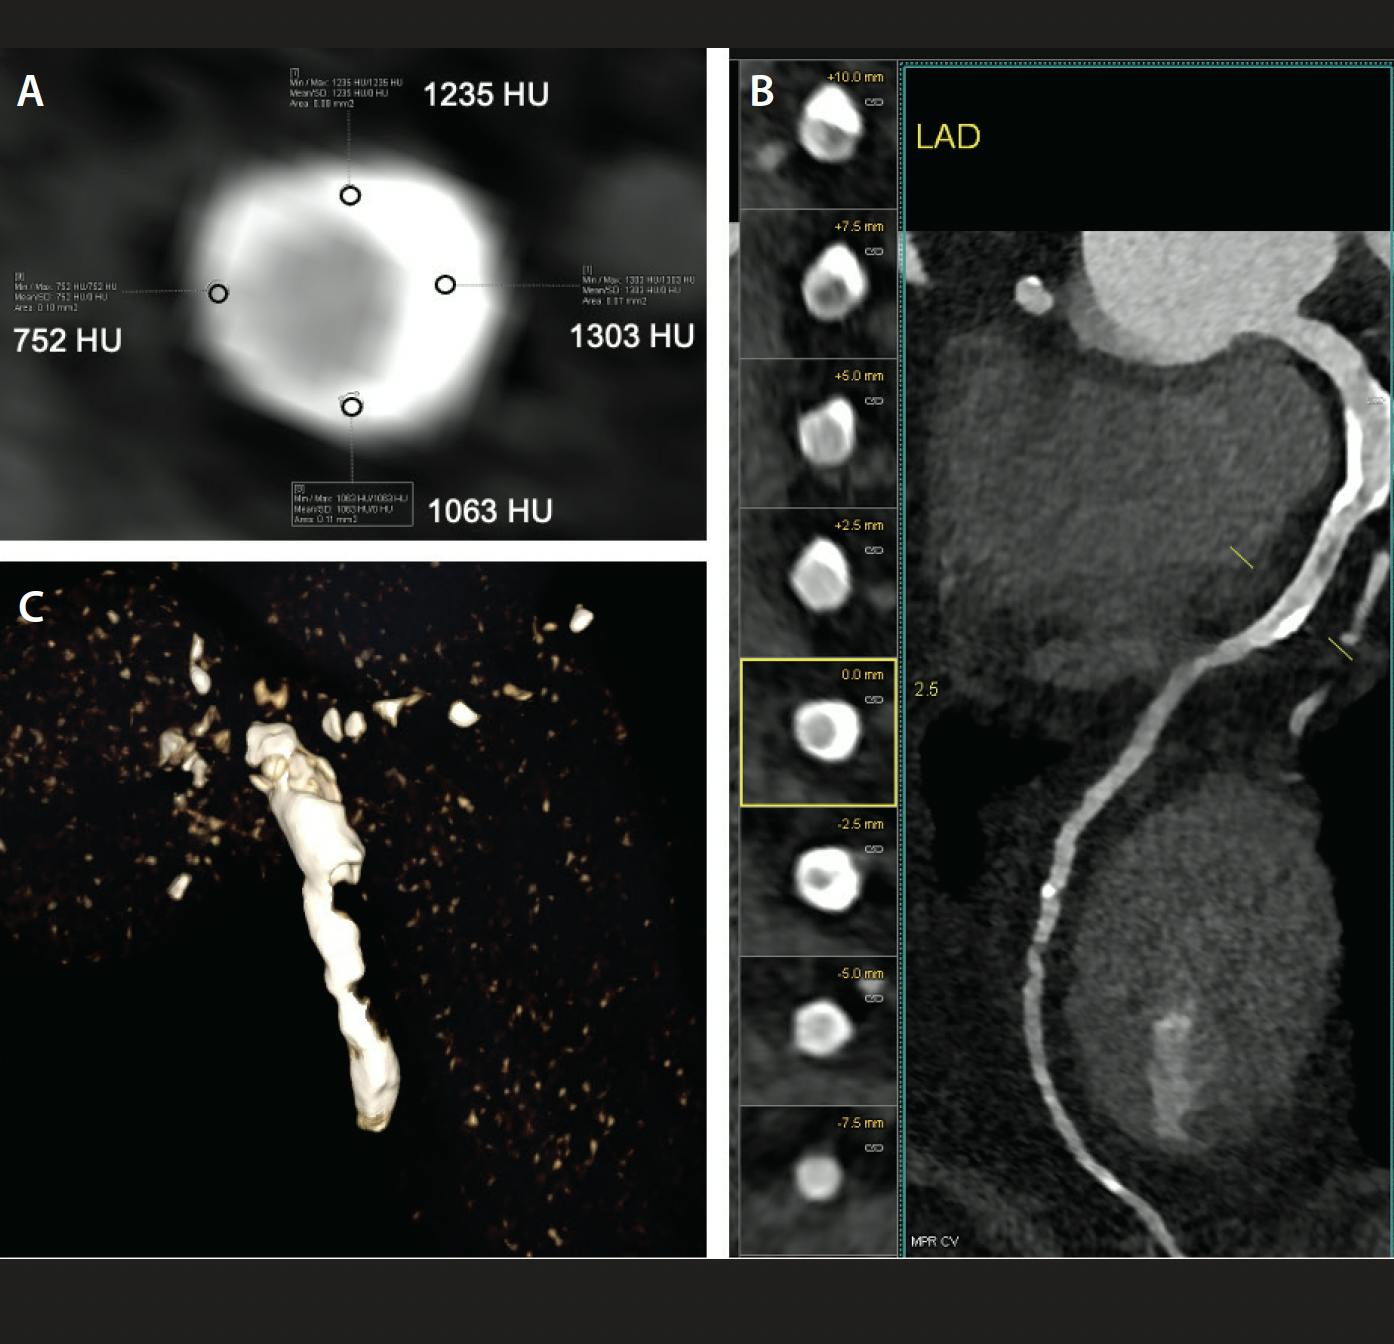

Similar to IVI, CCTA can provide detailed information on plaque characteristics, including CAC (Figure 2). A study by Monizzi et al suggested that CCTA-derived calcium arc, thickness, and length are reliable using OCT as a reference, although volumetric measurement of CAC by CCTA can be overestimated by 60%.8,14,15 Therefore, CCTA can provide a unique opportunity to evaluate characteristics of CAC associated with suboptimal procedural results even before bringing the patient to the catheterization laboratory.15 For example, a per-lesion calcium score ≥ 453 and calcification arc ≥ 270° on CCTA can suggest the need for rotational atherectomy.14 One of the CCTA features that cannot be assessed by IVI is calcium density measured in Hounsfield units (HU), which reflects resilience and resistance to fracture.15 Calcified lesions with higher HU are less likely to be fractured during PCI than those with lower HU (Figure 2A) and thus may benefit from up-front advanced calcium modification therapies.15,16 Last but not least, CCTA with three-dimensional (3D) reconstruction can help operators understand calcium distribution in longitudinal and circumferential extension and location in relation to vessel circumference and predict wire position and bias (Figure 2B and 2C).15 This information can help not only guide PCI but also choose the appropriate advanced calcium modification therapy, especially because unfavorable wire bias will reduce the efficacy of atherectomy while increasing the risk of complications.

Figure 2. CCTA calcium assessment. Cross-sectional assessment of calcium distribution, arc, thickness, and density (in HU) by CCTA (A). CCTA 3D reconstruction helps delineate calcium distribution in both longitudinal and circumferential extension (B, C).